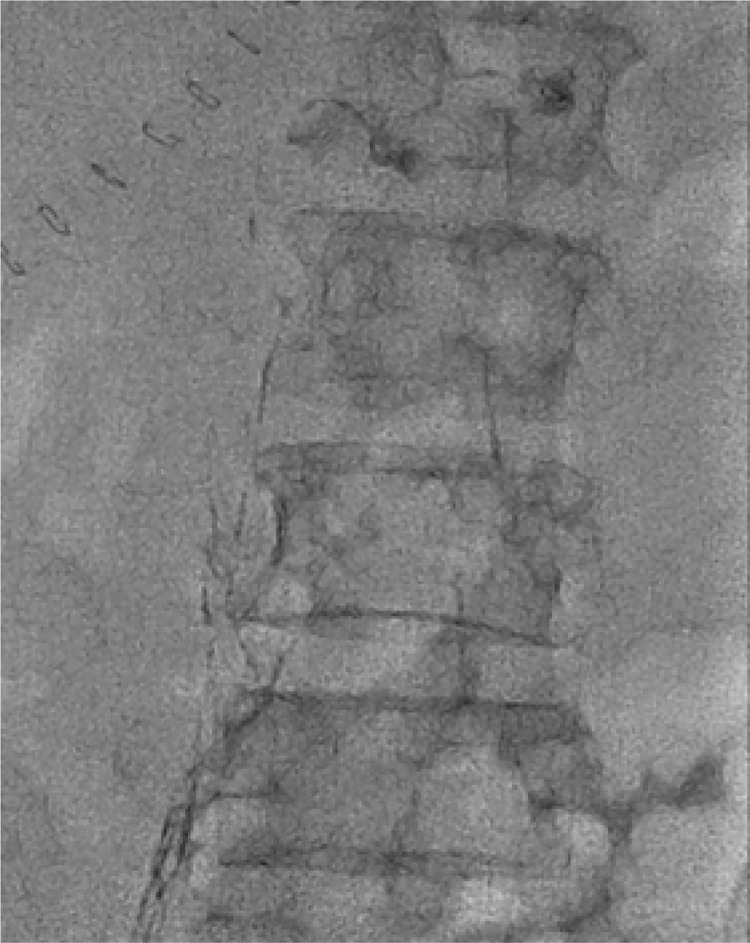

Results: Lymphangiography was successfully performed in all 10 patients. The average dosage of lipiodol used was 4.5 ml (range 3.5-7.0 ml). No procedure-related complications were observed after excluding unrelated factors. During lymphangiography, lipiodol leakage was directly observed in 3 cases, and in the other 5 cases, it was detected through abdominal computed tomography post-lymphangiography. Chylous ascites resolved solely through lymphangiography in 6 patients without requiring additional surgical intervention.